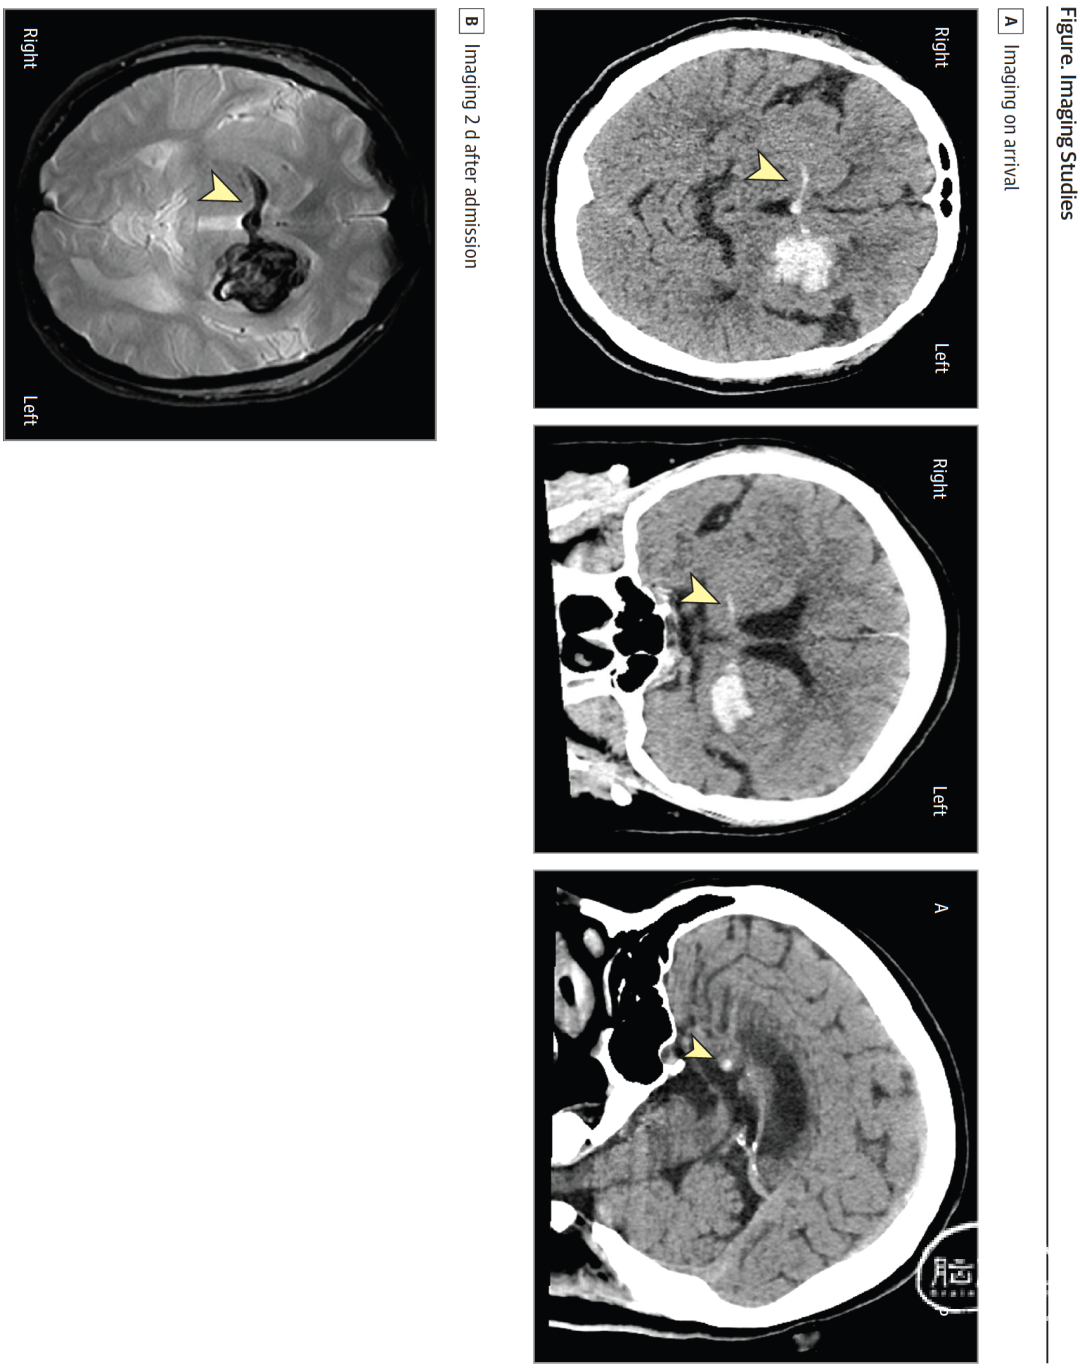

头颅CT平扫显示左侧基底节区(累及苍白球与壳核)高密度病灶,提示颅内出血(估算血肿量8.1 mL)。值得注意的是,一条异常线性高密度影从出血灶水平延伸至对侧(图A),该高密度影可能沿前连合后肢走行,这条通路从腹侧苍白球发出,穿过第三脑室前壁。2天后进行的脑部磁共振成像显示,沿前连合走行方向可见"车把样"含铁血黄素沉积,从左基底节血肿向对侧投射(图B)。磁共振血管造影未发现血管异常。

下图:A、入院时头颅CT显示线性出血灶(箭头所示)从左基底节区水平延伸,经前连合贯穿至对侧。B、入院2天后T2*加权磁共振成像显示,沿前连合走行方向可见车把样含铁血黄素沉积(箭头所示),该征象源自左基底节区血肿。图中A代表前方位,P代表后方位: